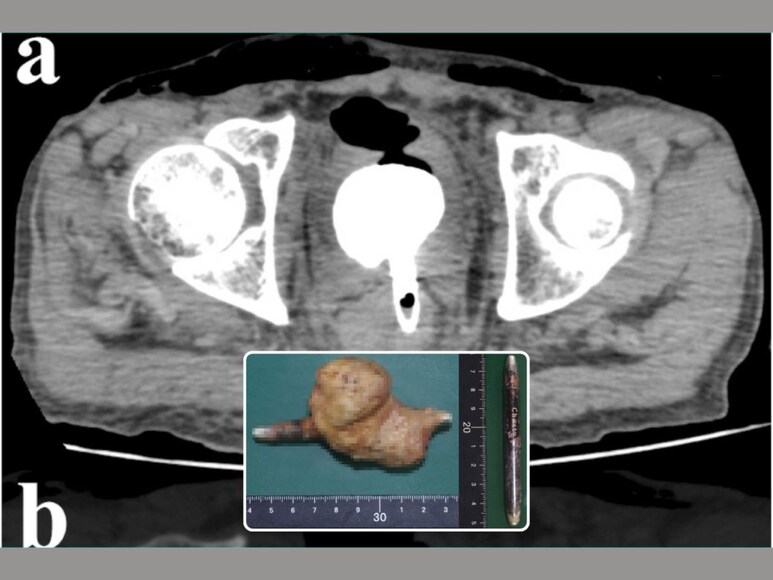

अस्पताल पहुंचने के बाद डॉक्टरों ने उन्हें बचाने की पूरी कोशिश की, लेकिन दो दिन के इलाज के बाद भी उनकी जान नहीं बचाई जा सकी. अपनी मृत्यु से दो सप्ताह पहले, उन्होंने भूख न लगने और दस्त की शिकायत की थी, और पिछले तीन वर्षों से रुक-रुक कर पेट दर्द से भी पीड़ित थे। शुरुआत में मौत का कारण स्पष्ट नहीं था, इसलिए शव को पोस्टमार्टम के लिए भेज दिया गया। जब फोरेंसिक रोगविज्ञानियों ने जांच शुरू की, तो उन्हें मलाशय के अंदर 9 सेमी लंबा और 0.8 सेमी चौड़ा एक एल्यूमीनियम आईलाइनर मिला। हैरानी की बात तो यह थी कि उस आईलाइनर पर अभी भी ब्रांड का नाम साफ नजर आ रहा था। लेकिन सबसे भयावह दृश्य तो यह था कि उस आईलाइनर के पास 6.5x6x4 सेमी का एक विशाल पत्थर बन गया था।

आदमी के मलाशय में आईलाइनर और पत्थर पाए गए।

जांच से पता चला कि यह विदेशी वस्तु (आईलाइनर) मलाशय की दीवार को छेदकर मूत्राशय के पिछले हिस्से में घुस गई थी। इस स्थिति के कारण शरीर के आंतरिक अंगों को भारी नुकसान हुआ। शख्स की एक किडनी सूज कर लाल हो गई थी, जबकि दूसरी पीली हो गई थी. किडनी से मूत्राशय तक मूत्र ले जाने वाली नली पूरी तरह से खिंच गई थी। डॉक्टरों ने मौत का कारण किडनी में गंभीर संक्रमण बताया है। शख्स के शरीर के अंदर जहर फैल गया था, जिसके कारण उसके अंगों ने काम करना बंद कर दिया था. पुलिस ने इस मामले की गहन जांच शुरू की कि आखिर वहां तक आईलाइनर कैसे पहुंचा. जांच के दौरान पता चला कि वह शख्स अक्सर महिलाओं के कपड़े पहनने का शौकीन था और उसके बेडरूम से कुछ यौन उपकरण (वाइब्रेटर) भी बरामद हुए थे।